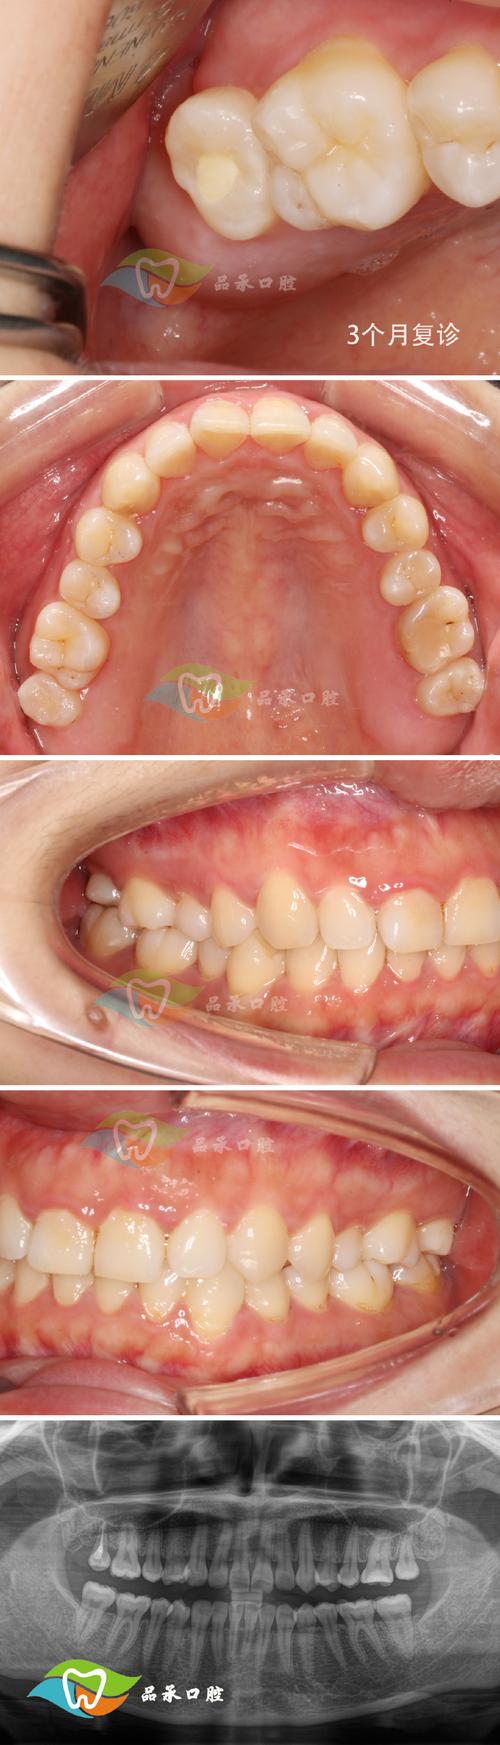

- GTR术后愈合期:

- 通常需要3-6个月甚至更长时间,让新骨充分形成和成熟,期间定期复查。

- 使用不可吸收膜需在术后6-8个月二次手术取出。

- 正畸治疗阶段:

- 在确认骨组织愈合稳定、牙周状况良好后开始。

- 正畸医生制定详细的正畸计划,选择合适的矫治器(托槽、隐形矫治器等)。

- 关键: 施加轻柔、持续、间歇的矫治力,避免过大力量干扰新生骨组织,移动速度可能需要适当放慢。

- 正畸过程中需加强牙周维护,定期进行牙周专业洁治。

- 保持阶段:

正畸结束后,需佩戴保持器维持效果,此阶段牙周支持仍在改建中,需特别重视口腔卫生和定期牙周复查。